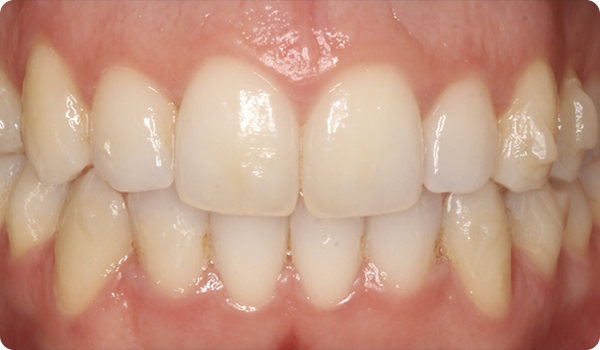

Efter en Right-behandling måste vi bevara patientens leende och förhindra att tänderna återgår till sin tidigare position.

Den slutliga uppföljningen av Right-behandlingen gör det möjligt för oss att tillverka retentionssystemet, Right Retainer.

Leenden på plats

Med Right får dina patienter det leende de önskar, inom den tid de vill, på ett bekvämt och ”osynligt” sätt.